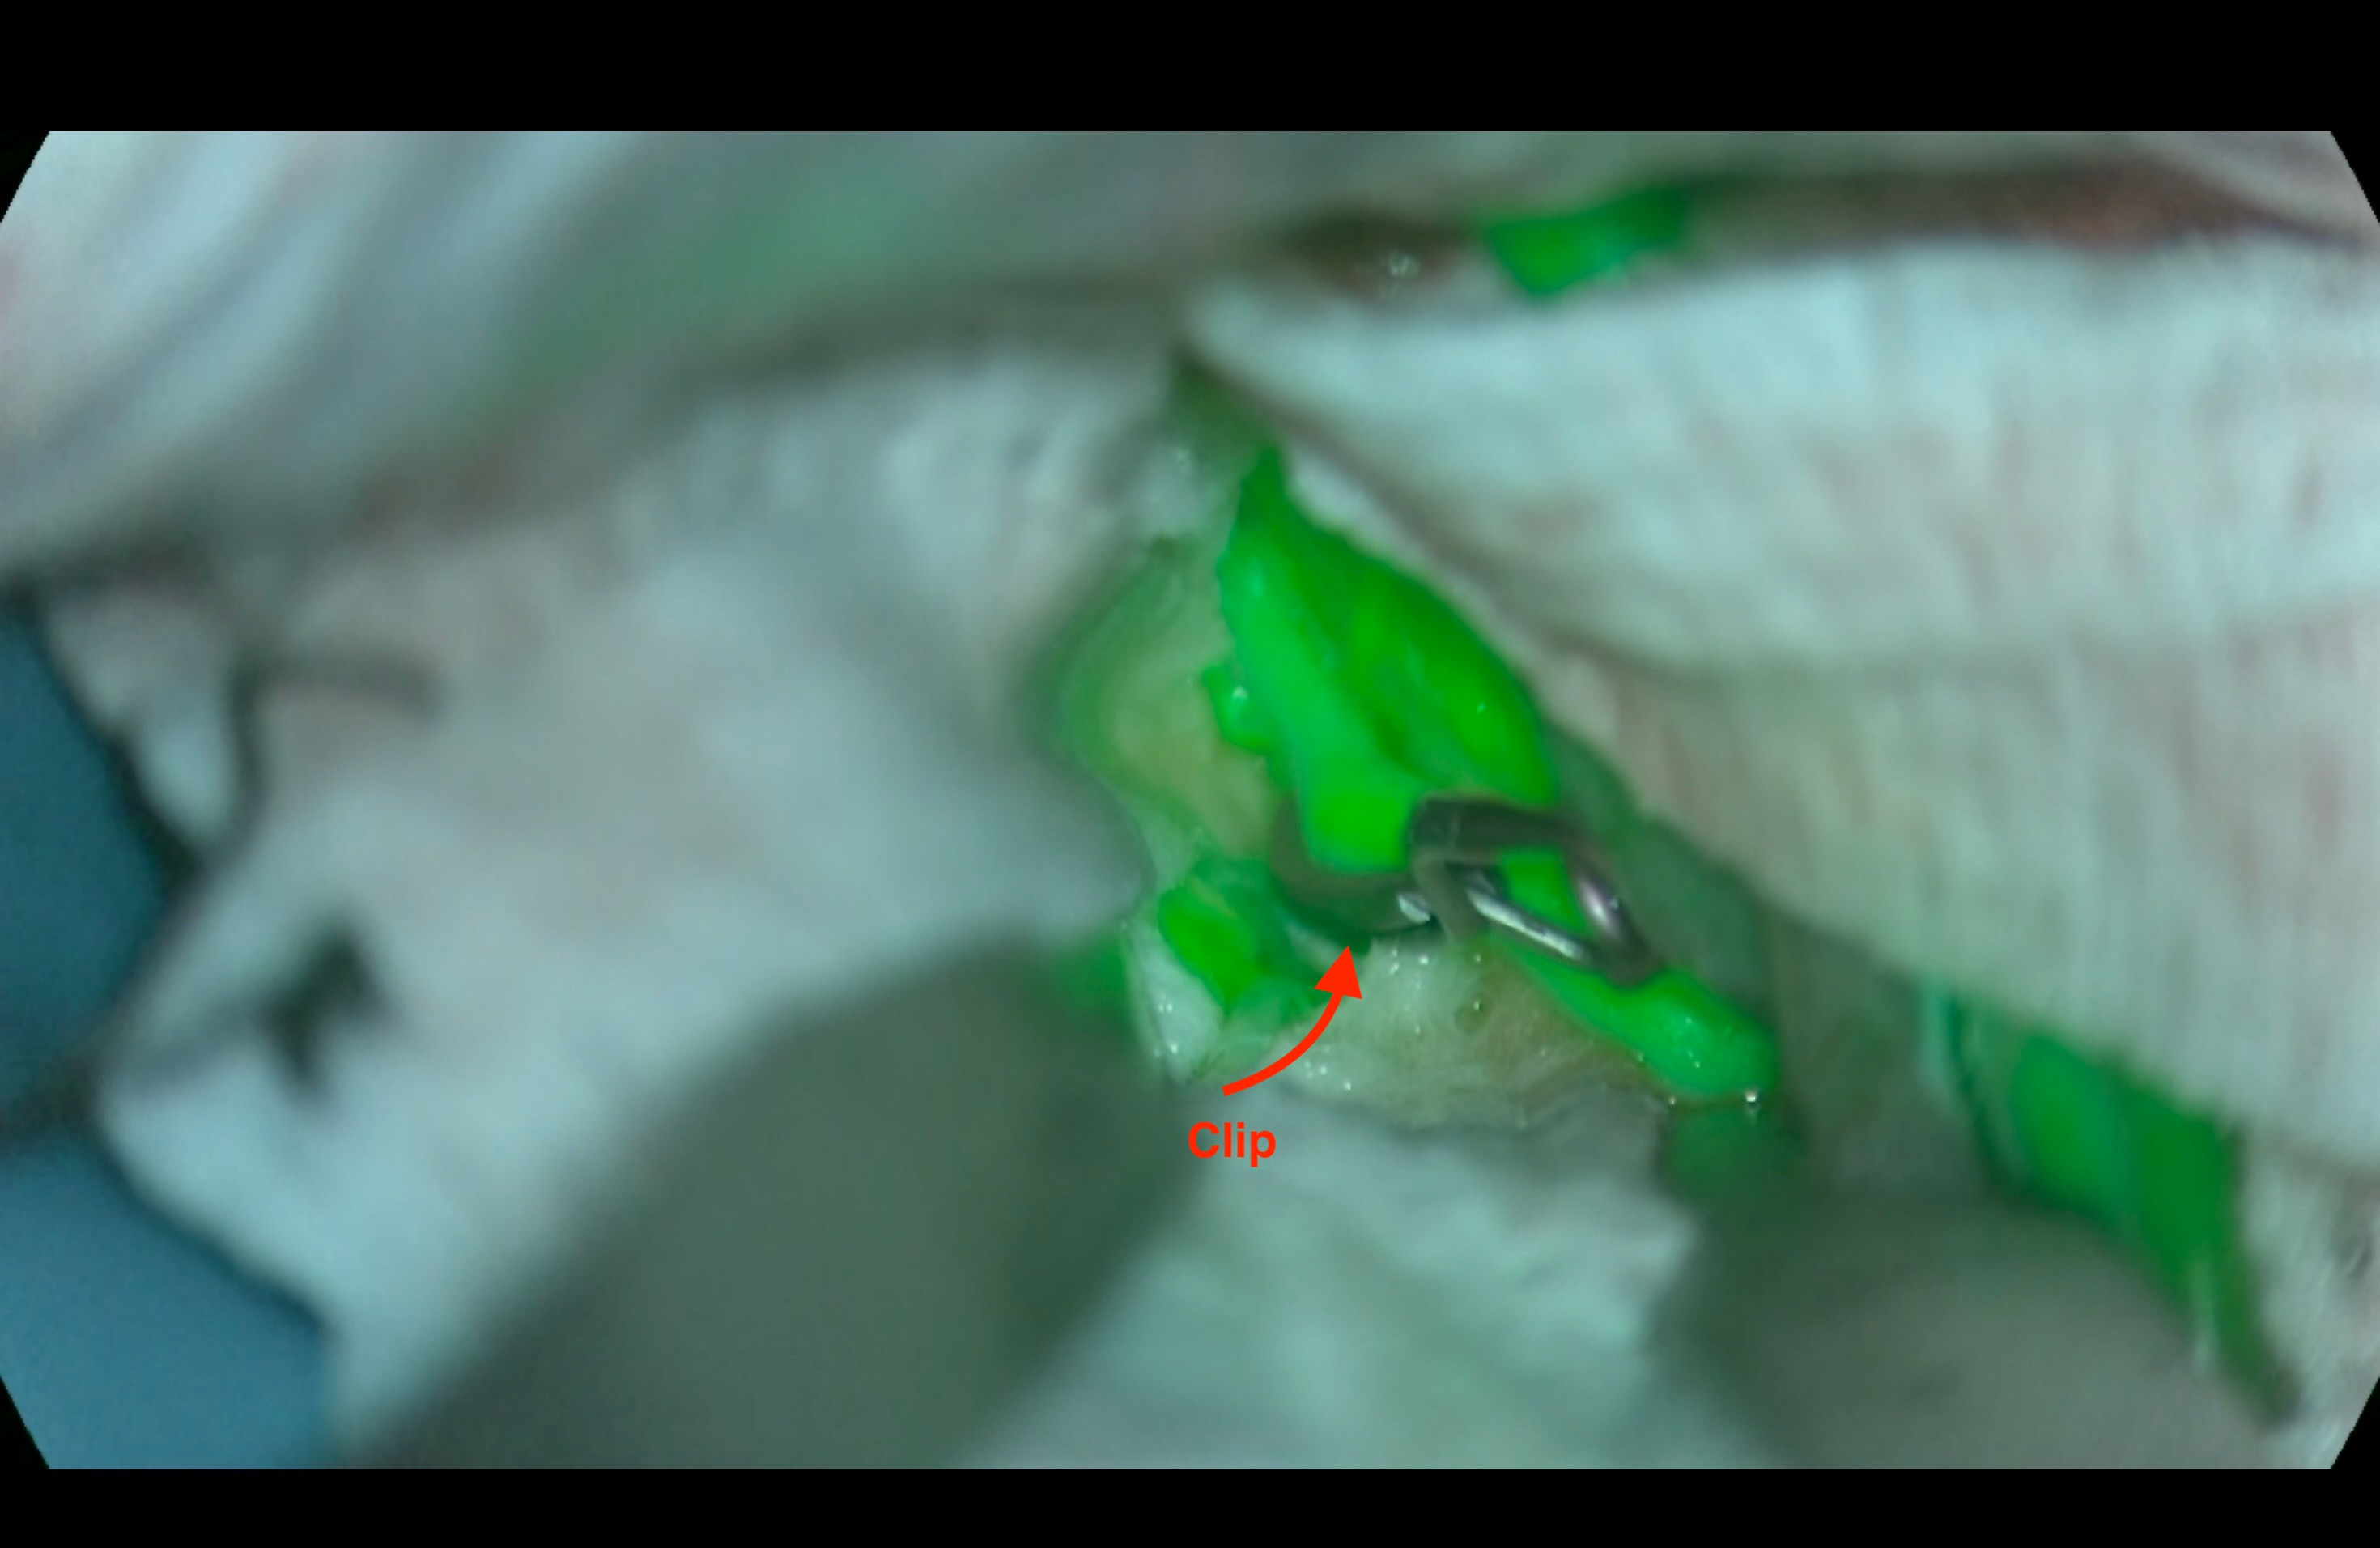

Διεγχειρητικά μπορούμε να διενεργήσουμε μια αγγειογραφία με φθορίζουσα ουσία (ICG), ώστε να αποφανθούμε αν έγινε αποκλεισμός όλου του ανευρύσματος. Στο εικόνα 1 απεικονίζεται ένα ανεύρυσμα της μέσης εγκεφαλικής αρτηρίας, όπως φαίνεται μετά από την διεγχειρητική  έγχυση φθορίζουσας ουσίας ενδοφλέβια. Στην εικόνα 2 φαίνεται ο πλήρης αποκλεισμός του ανευρύσματος μετά την τοποθέτηση μεταλλικού clip.

Εικόνα 2. Πλήρης αποκλεισμός του ανευρύσματος μετά την τοποθέτηση του clip. Το υγιές αγγείο απεικονίζεται πράσινο, το οποίο υποδηλώνει ανεμπόδιστη ροή του αίματος, ενώ το ανεύρυσμα δεν χρωματίζεται πλέον, γιατί έχει επέλθει πλήρης αποκλεισμός του από την κυκλοφορία

Στο βίντεο 1 φαίνεται το clip που τοποθετήθηκε στον αυχένα του ανευρύσματος, μετά την χορήγηση της φθορίζουσας ουσίας από την φλέβα του ασθενούς, θα χρωματισθούν πράσινα όσες αρτηρίες έχουν ροή, ενώ το ανεύρυσμα που έχει πλέον κλείσει δεν εμφανίζεται.

Βίντεο 1. Τοποθέτηση clip σε ένα αποτιτανωμένο ανεύρυσμα (φαίνεται το άσπρο στον θόλο του ανευρύσματος). Μετά την χορήγηση της φθορίζουσας ουσίας παρατηρείται ροή μόνο στο υγιές μέρος του αγγείου.